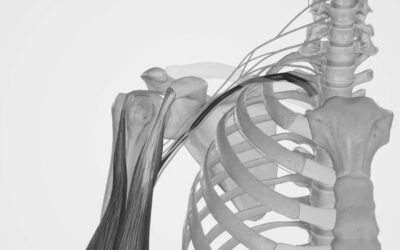

9 de cada 10 accidentes en moto suponen la lesión del plexo braquial: ¿Qué hacer cuando no se llega a tiempo?

Las lesiones del plexo braquial pueden tener un impacto devastador en la vida de los pacientes. Esta amenaza pone de relieve la importancia de la detección temprana y de la formación y práctica necesaria para poder tratarlas y de evitar que ocurran dentro del propio entorno sanitario.

Plexo braquial: claves para conocerlo en profundidad

Un sólido conocimiento anatómico se configura como factor imprescindible para dominar los bloqueos de plexos y realizar la técnica de forma segura y eficaz. Únicamente mediante una comprensión clara del cuerpo humano es posible realizar un abordaje correcto. El bloqueo del plexo braquial es uno de los métodos anestésicos más utilizados para la cirugía del miembro torácico.

Con todo, existen diversas complicaciones, generalmente debidas a una falta de habilidad o experiencia del profesional. Estas pueden llegar a ser fatales para el paciente

Efectos secundarios y complicaciones en el bloqueo del plexo braquial: prevención, manejo y recomendaciones

Saber realizar un correcto bloqueo del plexo braquial es clave para evitar graves consecuencias. La intoxicación sistémica o la parálisis permanente son algunos riesgos a los que se enfrenta el profesional sanitario.